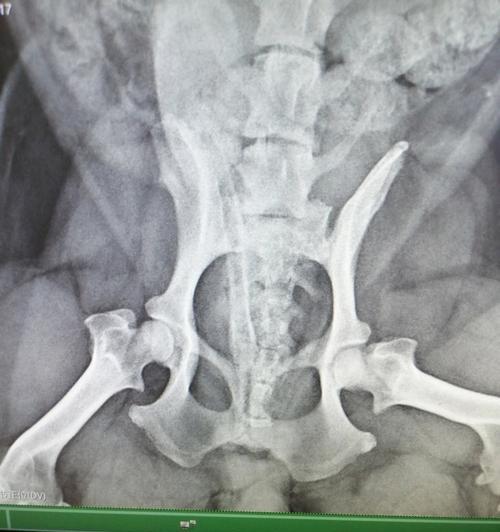

-配合兽医进行X光检查等诊断方法,以确诊腿髋坏死。

-腿髋坏死,也称为股骨头坏死,是一种骨骼疾病,常见于中小型犬。

-腿髋坏死的主要原因是血液供应不足导致股骨头缺血坏死。